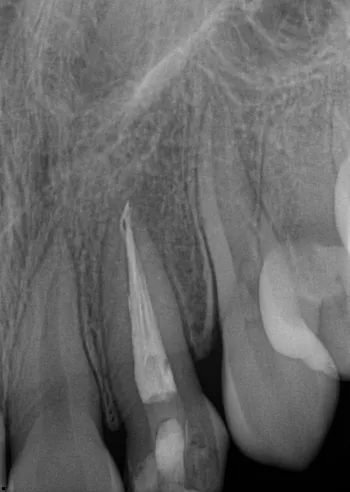

Before

After

9-year-old male sustained trauma to tooth #8 after being hit in the mouth.

2/9/23: Initial X-ray showed #8 with class I mobility. Tooth was splinted to #9. CBCT revealed a complete oblique radicular fracture with suspected palatal displacement.

6-month follow-up: CBCT showed stable fracture with no signs of periapical pathosis, bone loss, root resorption, or ankylosis.

1-year follow-up (8/7/24): CBCT comparison shows a traceable root canal and fully formed root with partial apical development compared to prior scans. Coronal and apical fragments remain in contact with early palatal fusion and decreased inter-radicular space. Surrounding periodontal structures are within normal limits.